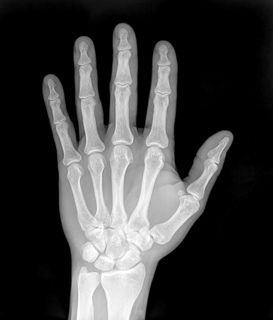

Different frequencies of EM radiation have different degrees of penetration. For example, if we take the human body as the object, visible light is reflected off the surface of the human body, ultra-violet light (from sunlight) damages the skin, but X-rays are able to penetrate the skin and bone and allow for pictures of the inside of the human body to be taken.

If we compare the energy of visible light to the energy of X-rays, we find that X-rays have a much higher frequency. Usually, electromagnetic radiation with higher frequency (energy) have a higher degree of penetration than those with low frequency.

X-rays

While X-rays are used significantly in medicine, prolonged exposure to X-rays can lead to cell damage and cancer.

For example, a mammogram is an X-ray of the human breast to detect breast cancer, but if a woman starts having regular mammograms when she is too young, her chances of getting breast cancer increases.